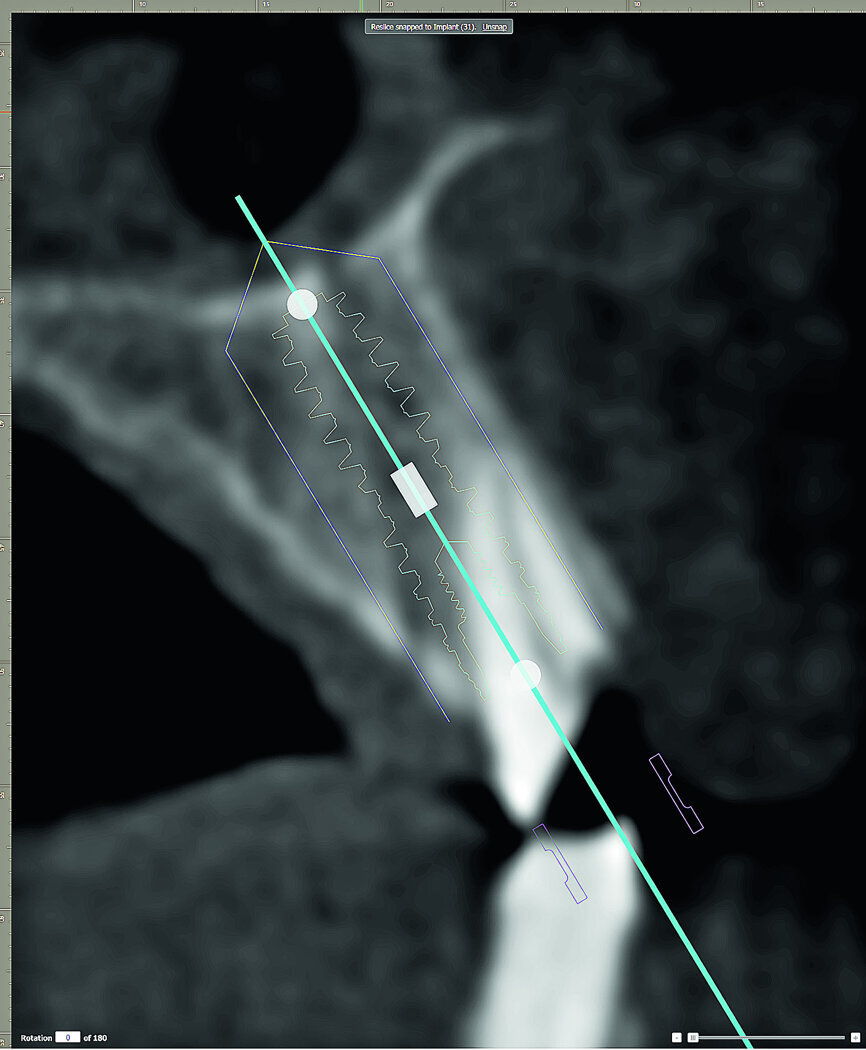

The initial review of the CBCT data was remarkable in the depiction of the thin, sharp, knife-edged alveolar ridge (Fig. 7). The 3-D volumetric reconstruction also reveals the position of the bilateral mental foramina and inferior alveolar nerves (seen in orange).

Contrary to the 2-D view of the panoramic radiograph, 3-D imaging and interactive treatment planning software allows clinicians to truly understand the patient's existing anatomy. For the example of the fully edentulous mandible, the CBCT scan revealed that the underlying bony ridge was quite sharp and uneven at the crest. This presentation would certainly not be favourable to place implants with a flapless surgical approach. In fact, to facilitate the placement of implants, and facilitate the restorative phase, it would be beneficial to flatten the irregular ridge to gain the appropriate and desired width at the alveolar crest (Fig. 8).

The CBCT data provides us with much more information and clinicians should consider ALL of the views afforded by the CBCT scan data and use the tools of the planning software to simulate the positioning of the implants, such as the axial and cross-sectional views. The right and left inferior alveolar nerves (IAN) were traced to determine the available width in the anterior symphysis for implant placement. It was determined that four standard diameter implants could be positioned to support an overdenture as desired by the patient (Fig. 9).